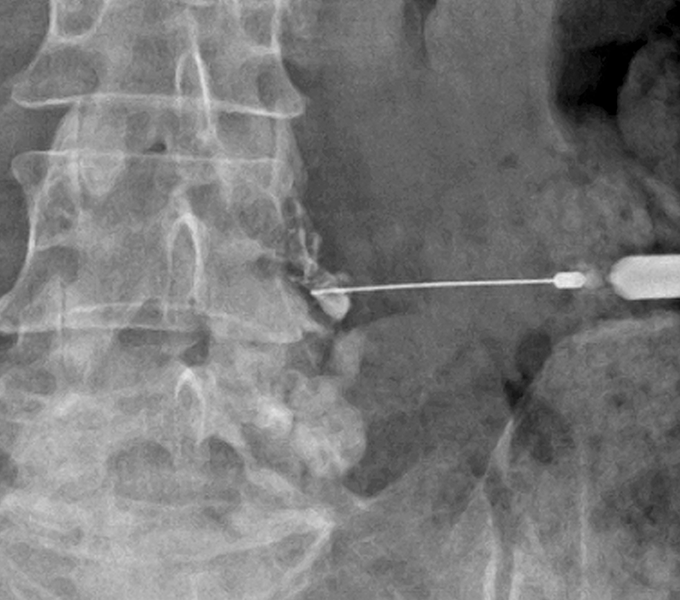

신경차단술

통증을 유발하는 신경 주위에 약물을 주입하여 통증 신호를 차단하는 치료입니다.

주로 만성 신경통이나 디스크 질환, 협착증 등으로 인한 심한 통증 완화에 사용됩니다.

• C-arm 정밀 시술

영상 장비(C-arm 등)를 통해

시술 정확도와 안전성을 높여

부작용을 최소화합니다.